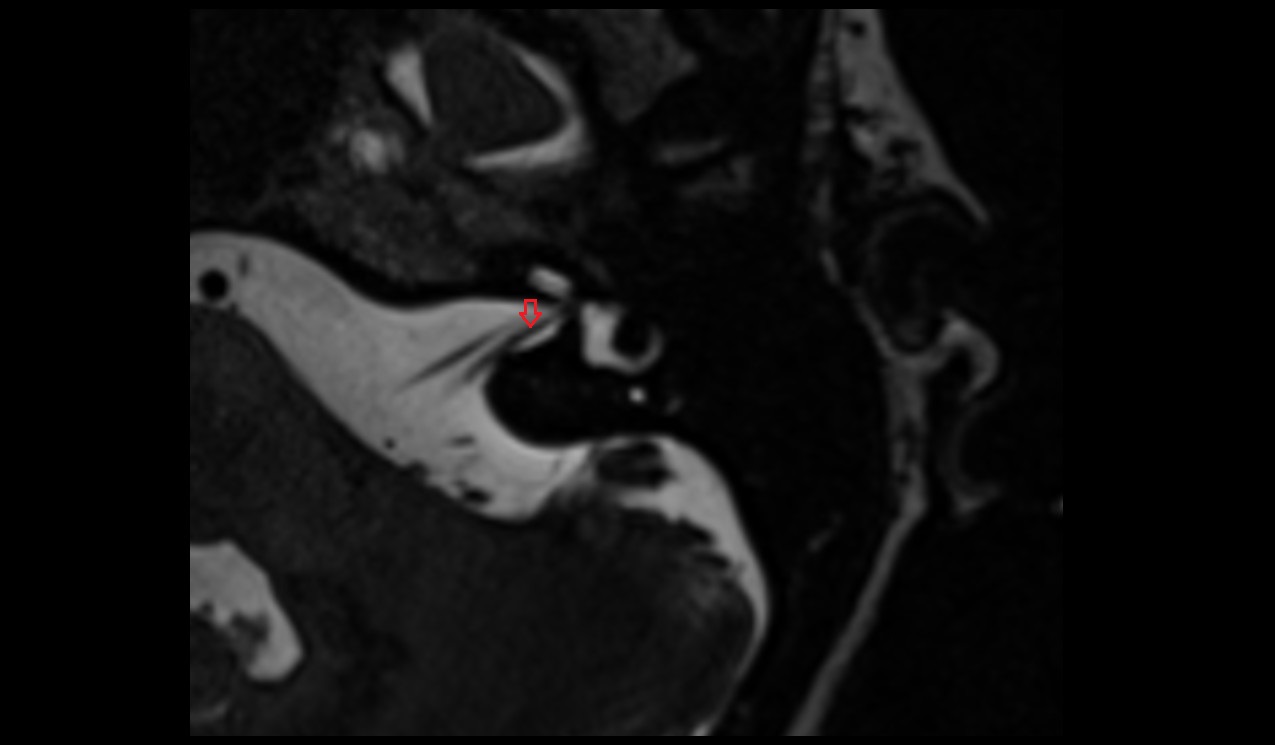

- Articular disc of temporomandibular joint

- Articular eminence

- Articular surface of mandibular fossa

- Articular tubercle

- Intermediate zone of articular disc

- Lateral temporomandibular ligament

- Temporomandibular joint

- Mandible

- Mandibular condyle

- Mandibular fossa